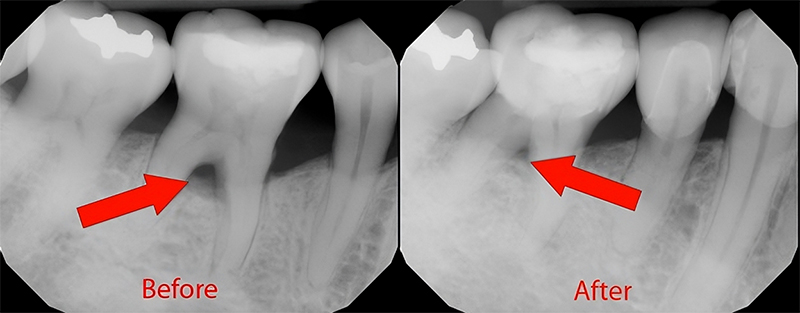

Periodontal disease is a chronic infection. Periodontal (gum) disease have been treated with gum surgeries for a long time. Slowly lasers have taken over the traditional surgeries. Today lasers have found applications in many fields. The use of lasers in dentistry is invaluable. Lasers emit thermal energy which, when directed to and absorbed by the targeted area, has the ability to coagulate and vaporize biological tissue.

The area to be treated is anaesthetized with minimal freezing. Once the client feels absolutely numb in that area, a mini flap is done to gain access to the deeper tissues. A deep cleaning is done followed by complete disinfection of the area with the laser light. Laser seals the pocket to allow the gum and bone support to repair itself. Post-operative instructions are given and follow up is done within a week.